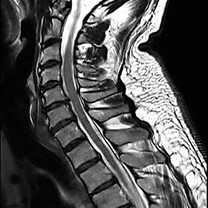

Die MRT (Magnetresonanztomographie), auch Kernspintomographie genannt, ist eine Untersuchung in einem Magnetfeld und benötigt keine Röntgenstrahlen. Mit ihr können alle Körperregionen überlagerungsfrei dargestellt werden. Wir führen hier die MRT fast aller Körperregionen, Organe und Blutgefäße durch.